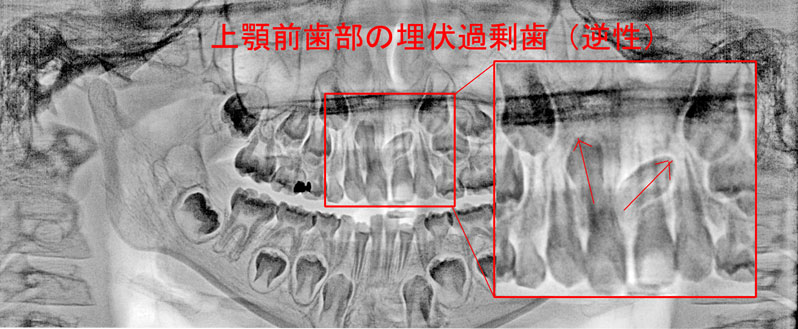

歯の生えてきた位置がおかしい場合。歯の数が多過ぎる場合、少ない場合。

歯並びの凸凹。歯並びの全体の形の不具合。上下の歯のかみ合わせの問題。

実際の歯列不正はさまざまな要因が重なって発生しています。